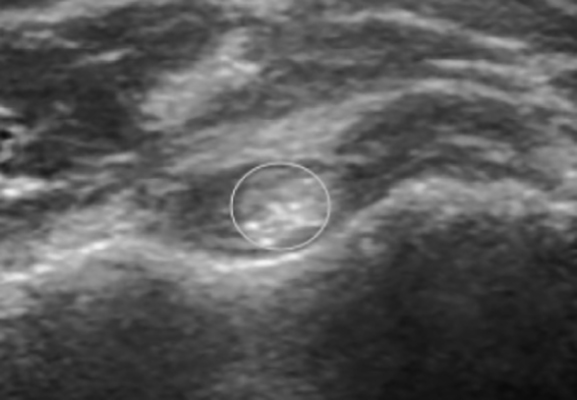

There will be localised tenderness, particularly over the biceps groove and proximal biceps

Image from OpenI – Licensed by CC